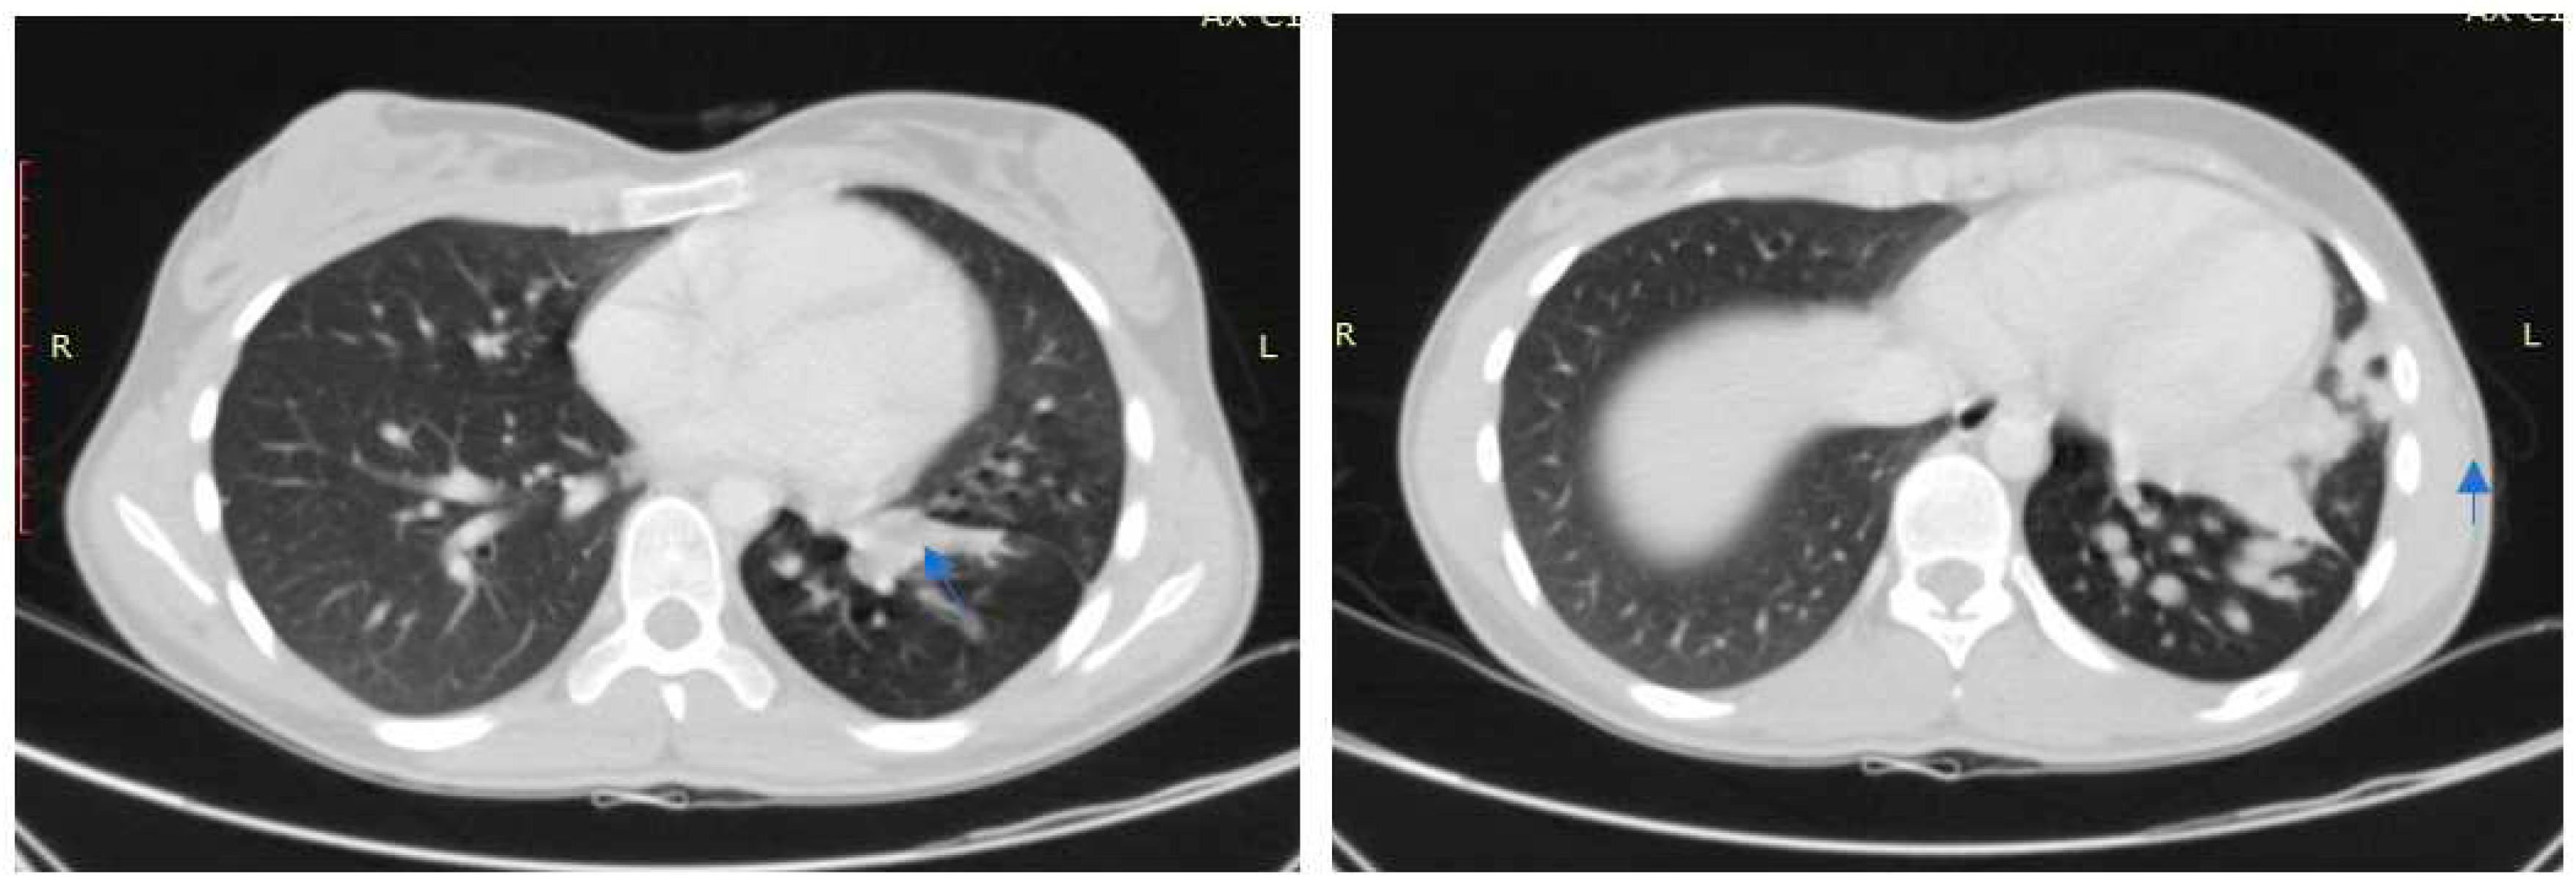

Case no 1.

Case no. 2